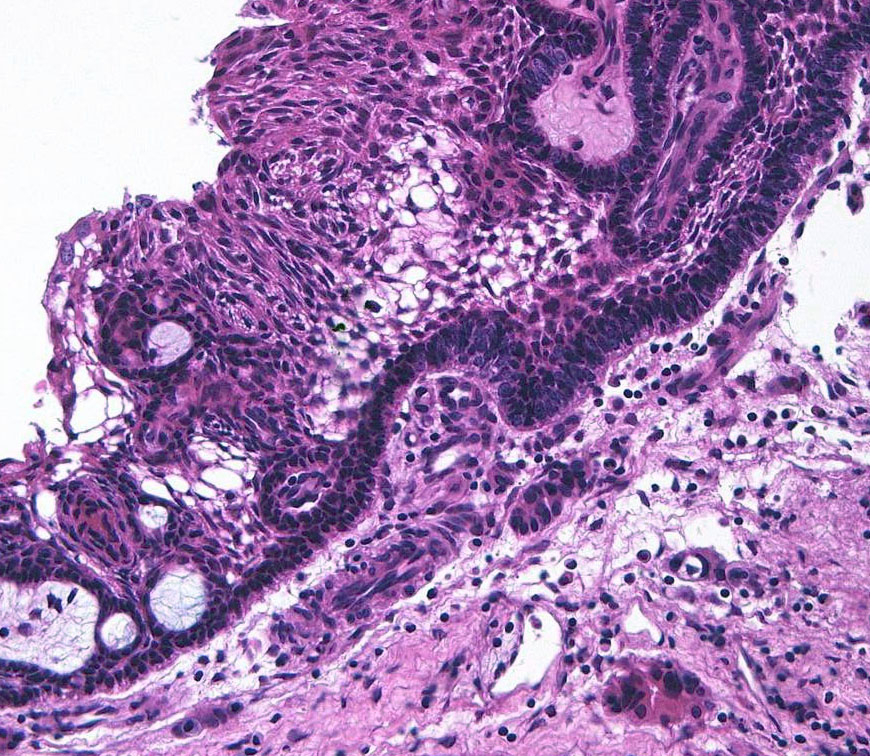

- 病理は,fibrovascular coreを中心として,ケラチンを含まない分化度の高い”非角化型”扁平上皮の単純な増殖です

成人の第3脳室内部に局在する頭蓋咽頭腫です。経脳梁法で両側のモンロー孔から全摘出しました。下垂体組織は残っています。これは乳頭状頭蓋咽頭腫と呼ばれるもので,成人にしか発生しません,のう胞がなく石灰化もないのが大きな特徴です。境界が明瞭で柔らかく摘出が簡単なタイプとして知られています。この患者さんも術後に下垂体機能不全も視床下部障害も生じませんでした。

Monomorphous mass of well-differenciated squamous epithelium lacking surface maturation and wet keratin.